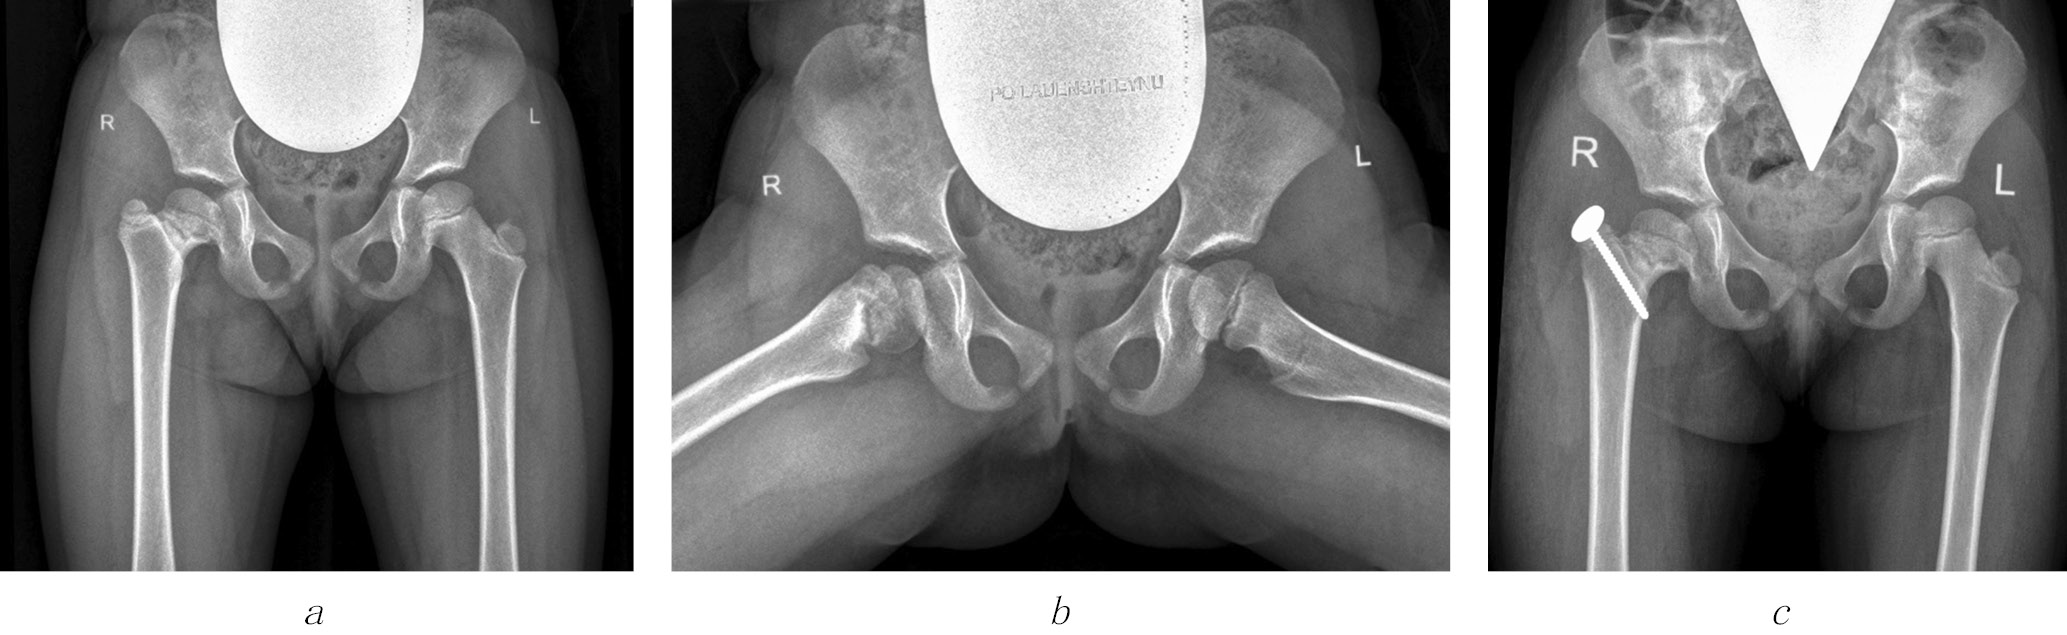

Fig. 3. Radiographs of patient K (9 years old) diagnosed with Perthes disease on the left side but was in the recovery stage: a, before surgery; b, 2.5 years after the trochanteric epiphysiodesis on the left